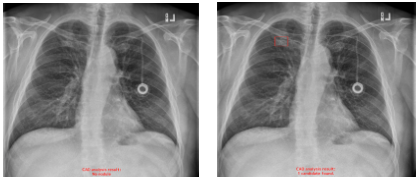

・偽陽性の改善例

肋骨,血管,ニップル等が重なり合い,透過度が減少している領域に対して旧モデルでは偽陽性が発生していたが,新モデルでは改善されている。(4)

※左:旧モデルによる解析結果,右:新モデルによる解析結果